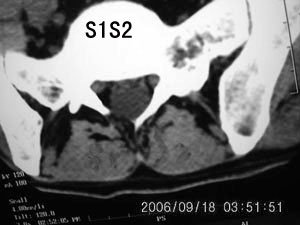

以下是引用守望可可西里在2006-9-18 21:29:00的发言:[br][br] 马尾肿瘤,密度较低,大部分似乎呈囊性变(看着很费眼),考虑室管膜瘤,建议mri。

以下是引用dyg在2006-9-18 22:27:00的发言:[br]正常脊髓.[br]分析:人的脊髓从枕大孔开始至腰1.2椎体为止,有2个生理膨大,分为颈膨大和腰膨大;该病人脊髓须然从腰段开始直至马尾似乎膨大,胆是与上段脊髓密度没有多大变化,所以我认为是正常膨大之延续;当然最好做ct增强或mri检查,排除肿瘤.

以下是引用飞虎在2006-9-18 20:18:00的发言:[br]部分椎管内密度不均且无ct值 故mri检查